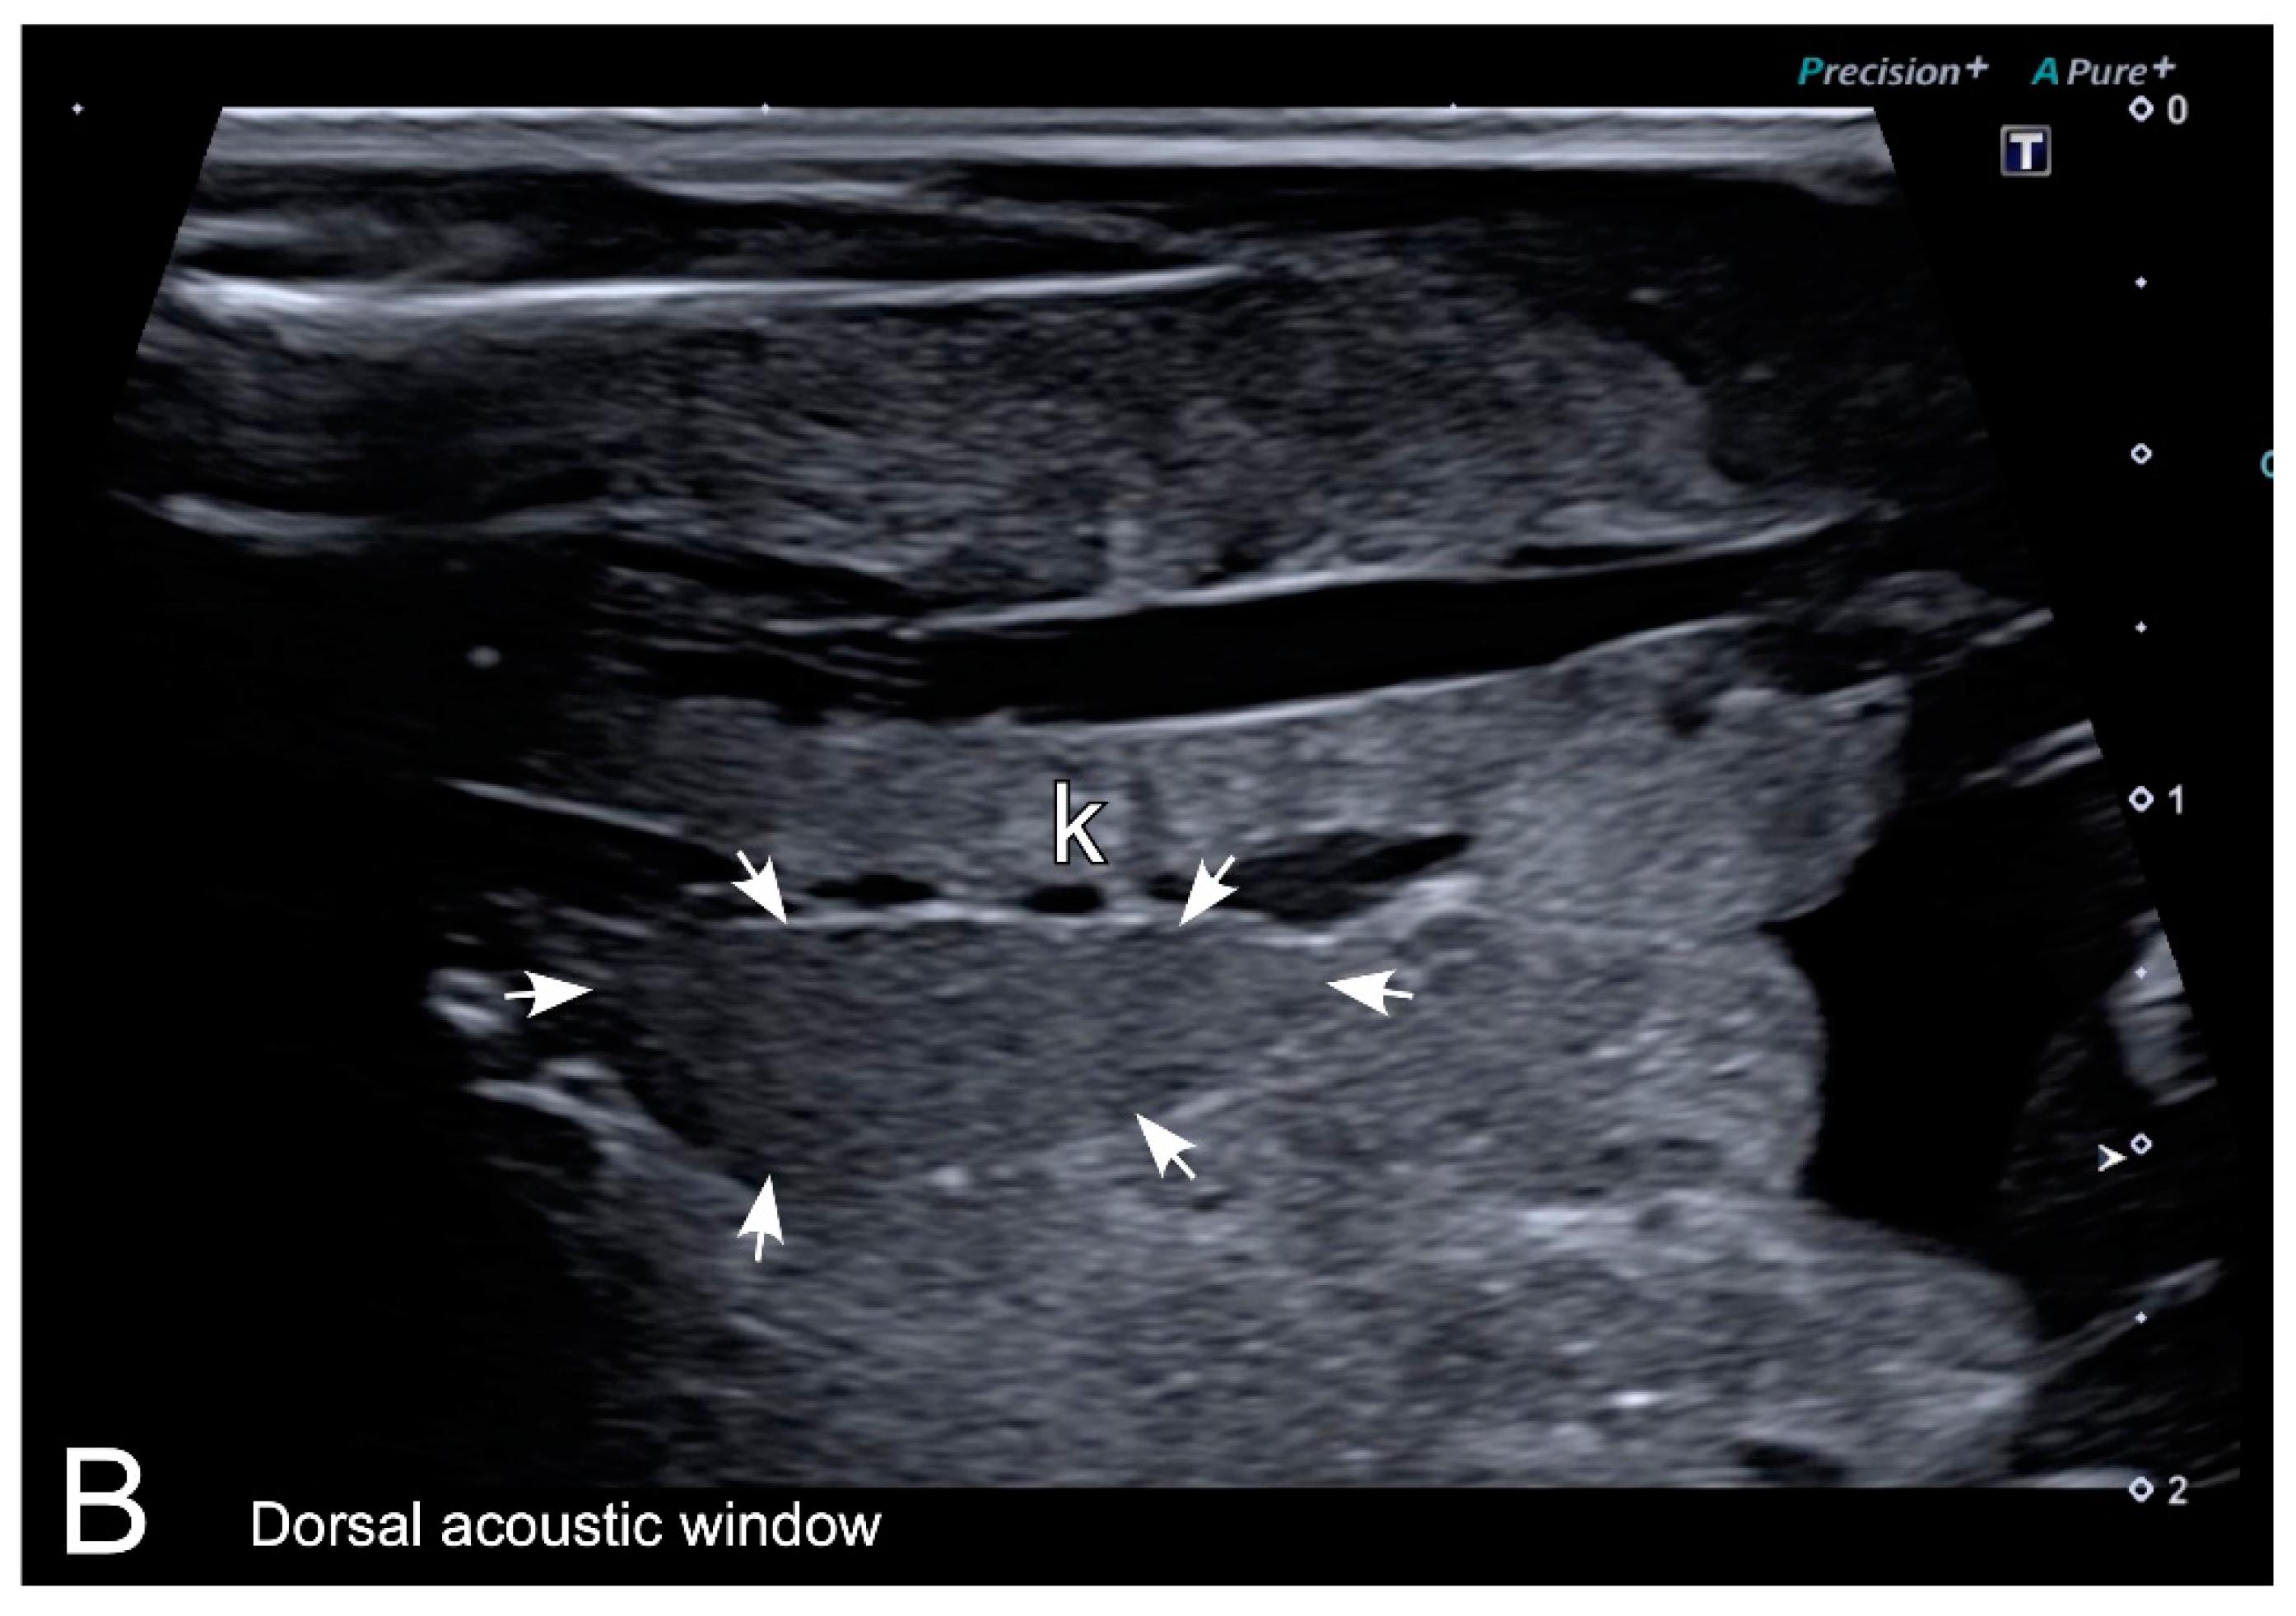

Figure 7. Representative HR-US images of Kaloula pulchra (A) and Xenopus laevis (B) males obtained in the longitudinal plane using a dorsal acoustic window. The testes (delimited by arrows) appeared as structures with oval morphology, mid echogenicity and homogenous echotexture. Testes were located just ventral or ventrolateral of the ipsilateral kidney (k).

|